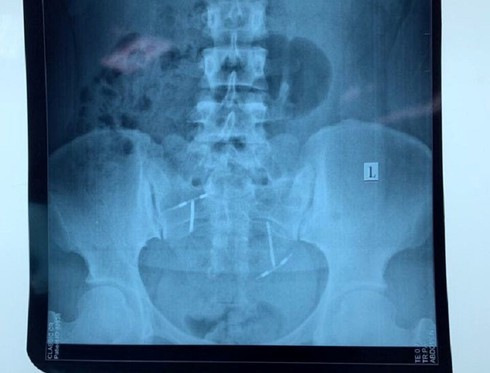

Sau khi thực hiện các xét nghiệm, chụp CT, chụp X-quang, hội chẩn các chuyên khoa, các bác sĩ phát hiện dị vật nằm trong bàng quang của chị L.

Vòng tránh thai hình chữ T. trong bàng quangcủa chị L. |

Trải qua gần một giờ phẫu thuật, ê-kíp của bệnh viện đã lấy ra một vòng tránh thai hình chữ T trong bàng quang của bệnh nhân. Hiện, sức khỏe của chị L. đang hồi phục và có thể xuất viện trong thời gian đến.